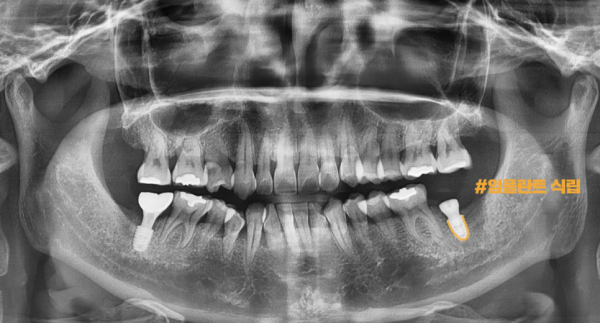

이 환자분께서는 오른쪽 치아 통증을 호소하셨는데요.

파노라마 엑스레이 사진을 보면 양쪽 어금니쪽에 모두 염증이 생겨 잇몸뼈가

녹아버린 상태로 보입니다. 이렇게 양쪽이 모두 상태가 안좋으면 더 문제가 큰 쪽부터

치료를 해야 하기 때문에 오른쪽 어금니부터 임플란트를 하기로 하였습니다.

This patient complained of right tooth pain.

If you look at the panoramic X-ray, both molars are inflamed, and the gum bones are

It looks like it's melted. If both sides are not in good condition, the bigger problem will start

Since I need to treat it, I decided to start with my right molar.